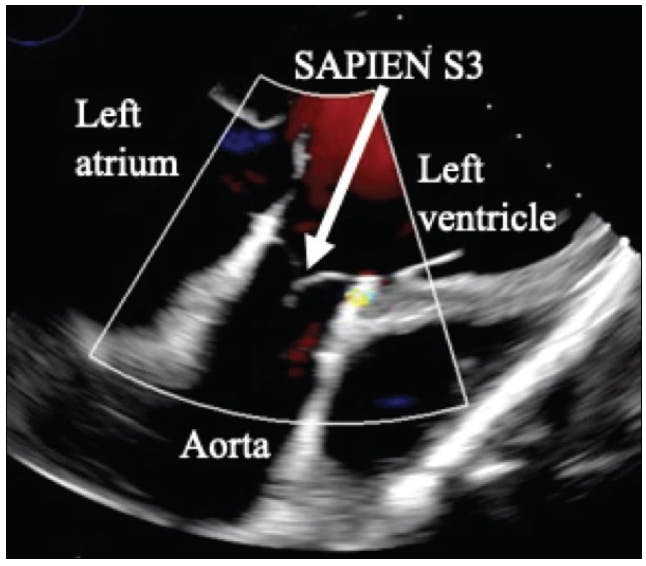

Device migration was also prominent in Yehya et al; nine patients with continuous-flow LV assist devices (CF-LVADs) underwent TAVR for AI, and 22% of patients required a second implant.13,14 Instead of a modified Park stitch, patch closure, SAVR, or Amplatzer device (Abbott), TAVR can be used in CF-LVAD patients with AI from static flow and altered hemodynamics (Figure 1). Concomitant treatment of existing greater than mild AI is recommended at the time of CF-LVAD placement and postimplantation; untreated AI will dampen device performance.13,14 In these extreme-risk surgical patients, a less invasive method of treatment is preferred. The results of Yehya et al were promising, with a decrease in AI to none/trace in all nine participants (Figure 2), 100% survival to discharge, and 89% survival at 6 months.13,14 However, along with migration, bleeding-related complications also occurred. One-third of patients had access site/vascular complications, and although not existent in this study, TAVR thrombosis for AI in CF-LVAD has been reported.13-15

Figure 1. Angiography of a CF-LVAD patient who received a balloon-expandable valve for AI.

Figure 2. Transgastric echocardiography demonstrating elimination of AI in a CF-LVAD patient with Sapien 3 TAVR valve placement.